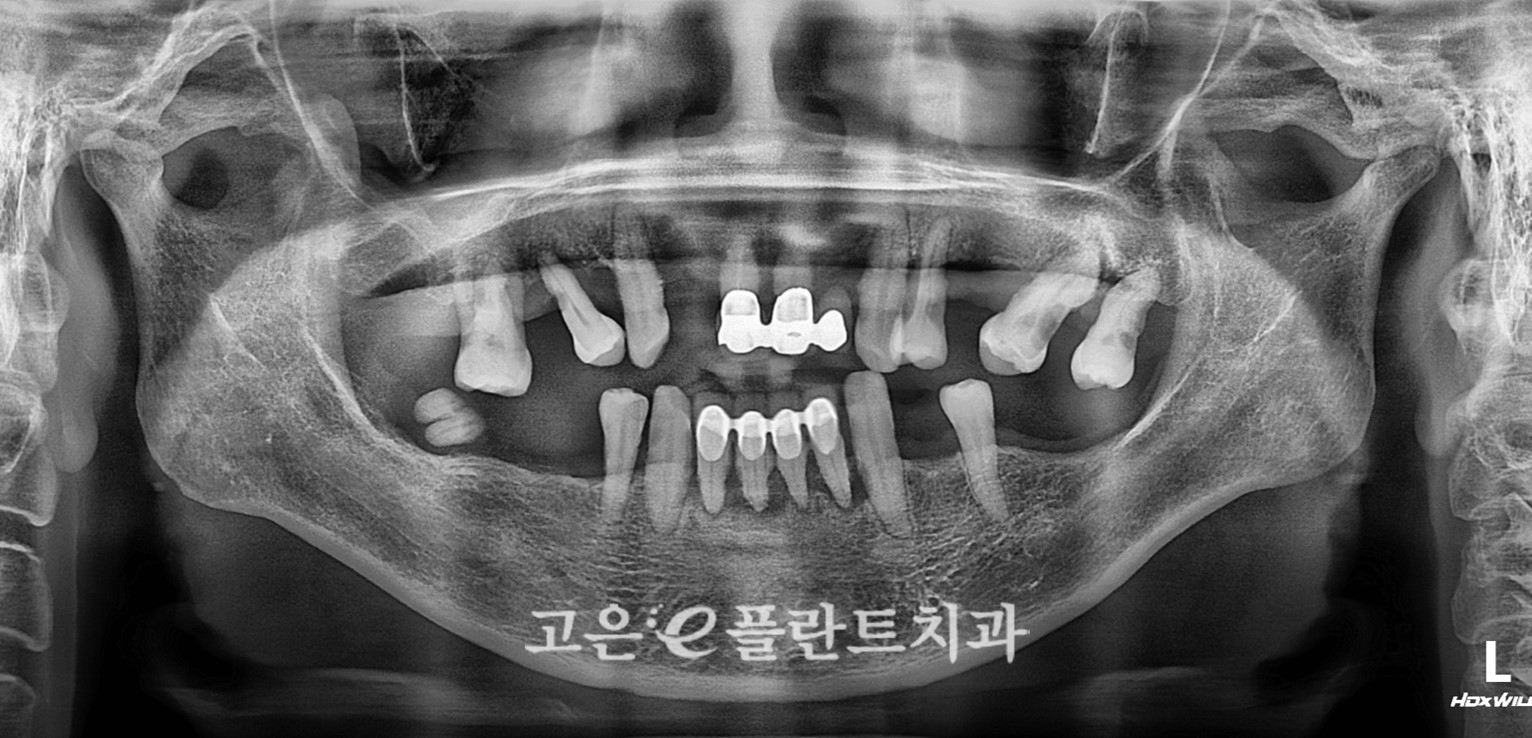

처음 내원하셨을 때,

윗니 앞니 쪽 보철물이 전체적으로 연결된 상태였는데 이미 많이 흔들리고 있었습니다.

겉으로 보기엔 앞니 보철이 조금 흔들리나 보다 하실 수 있지만,

잇몸과 뿌리 쪽을 자세히 보니

잇몸이 많이 내려가 있고, 치아 뿌리가 거의 다 노출되어 있으며

치주염으로 인해 잇몸뼈(치조골)가 상당 부분 녹아 있는 상태였습니다.

아랫니도 크게 다르지 않았습니다.

부분적으로 남아 있던 치아들이 대부분 치주염 말기 단계에 가까워

“어디 하나 튼튼하다”고 말하기 어려운 상황이었죠.